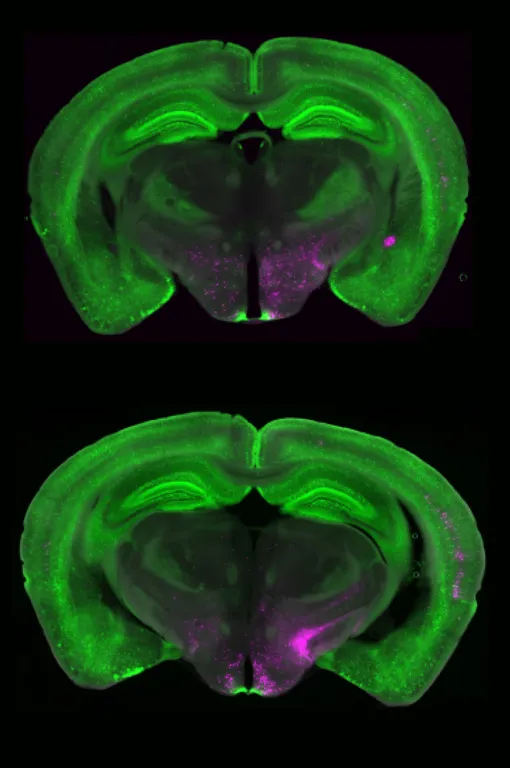

Ученые обнаружили особую группу нейронов в области мозга, которая называется литеральное парабрахиальное ядро (IPBN). Эти нервные клетки — «нейроны, экспрессирующие рецептор Y1», или просто нейроны Y1R.